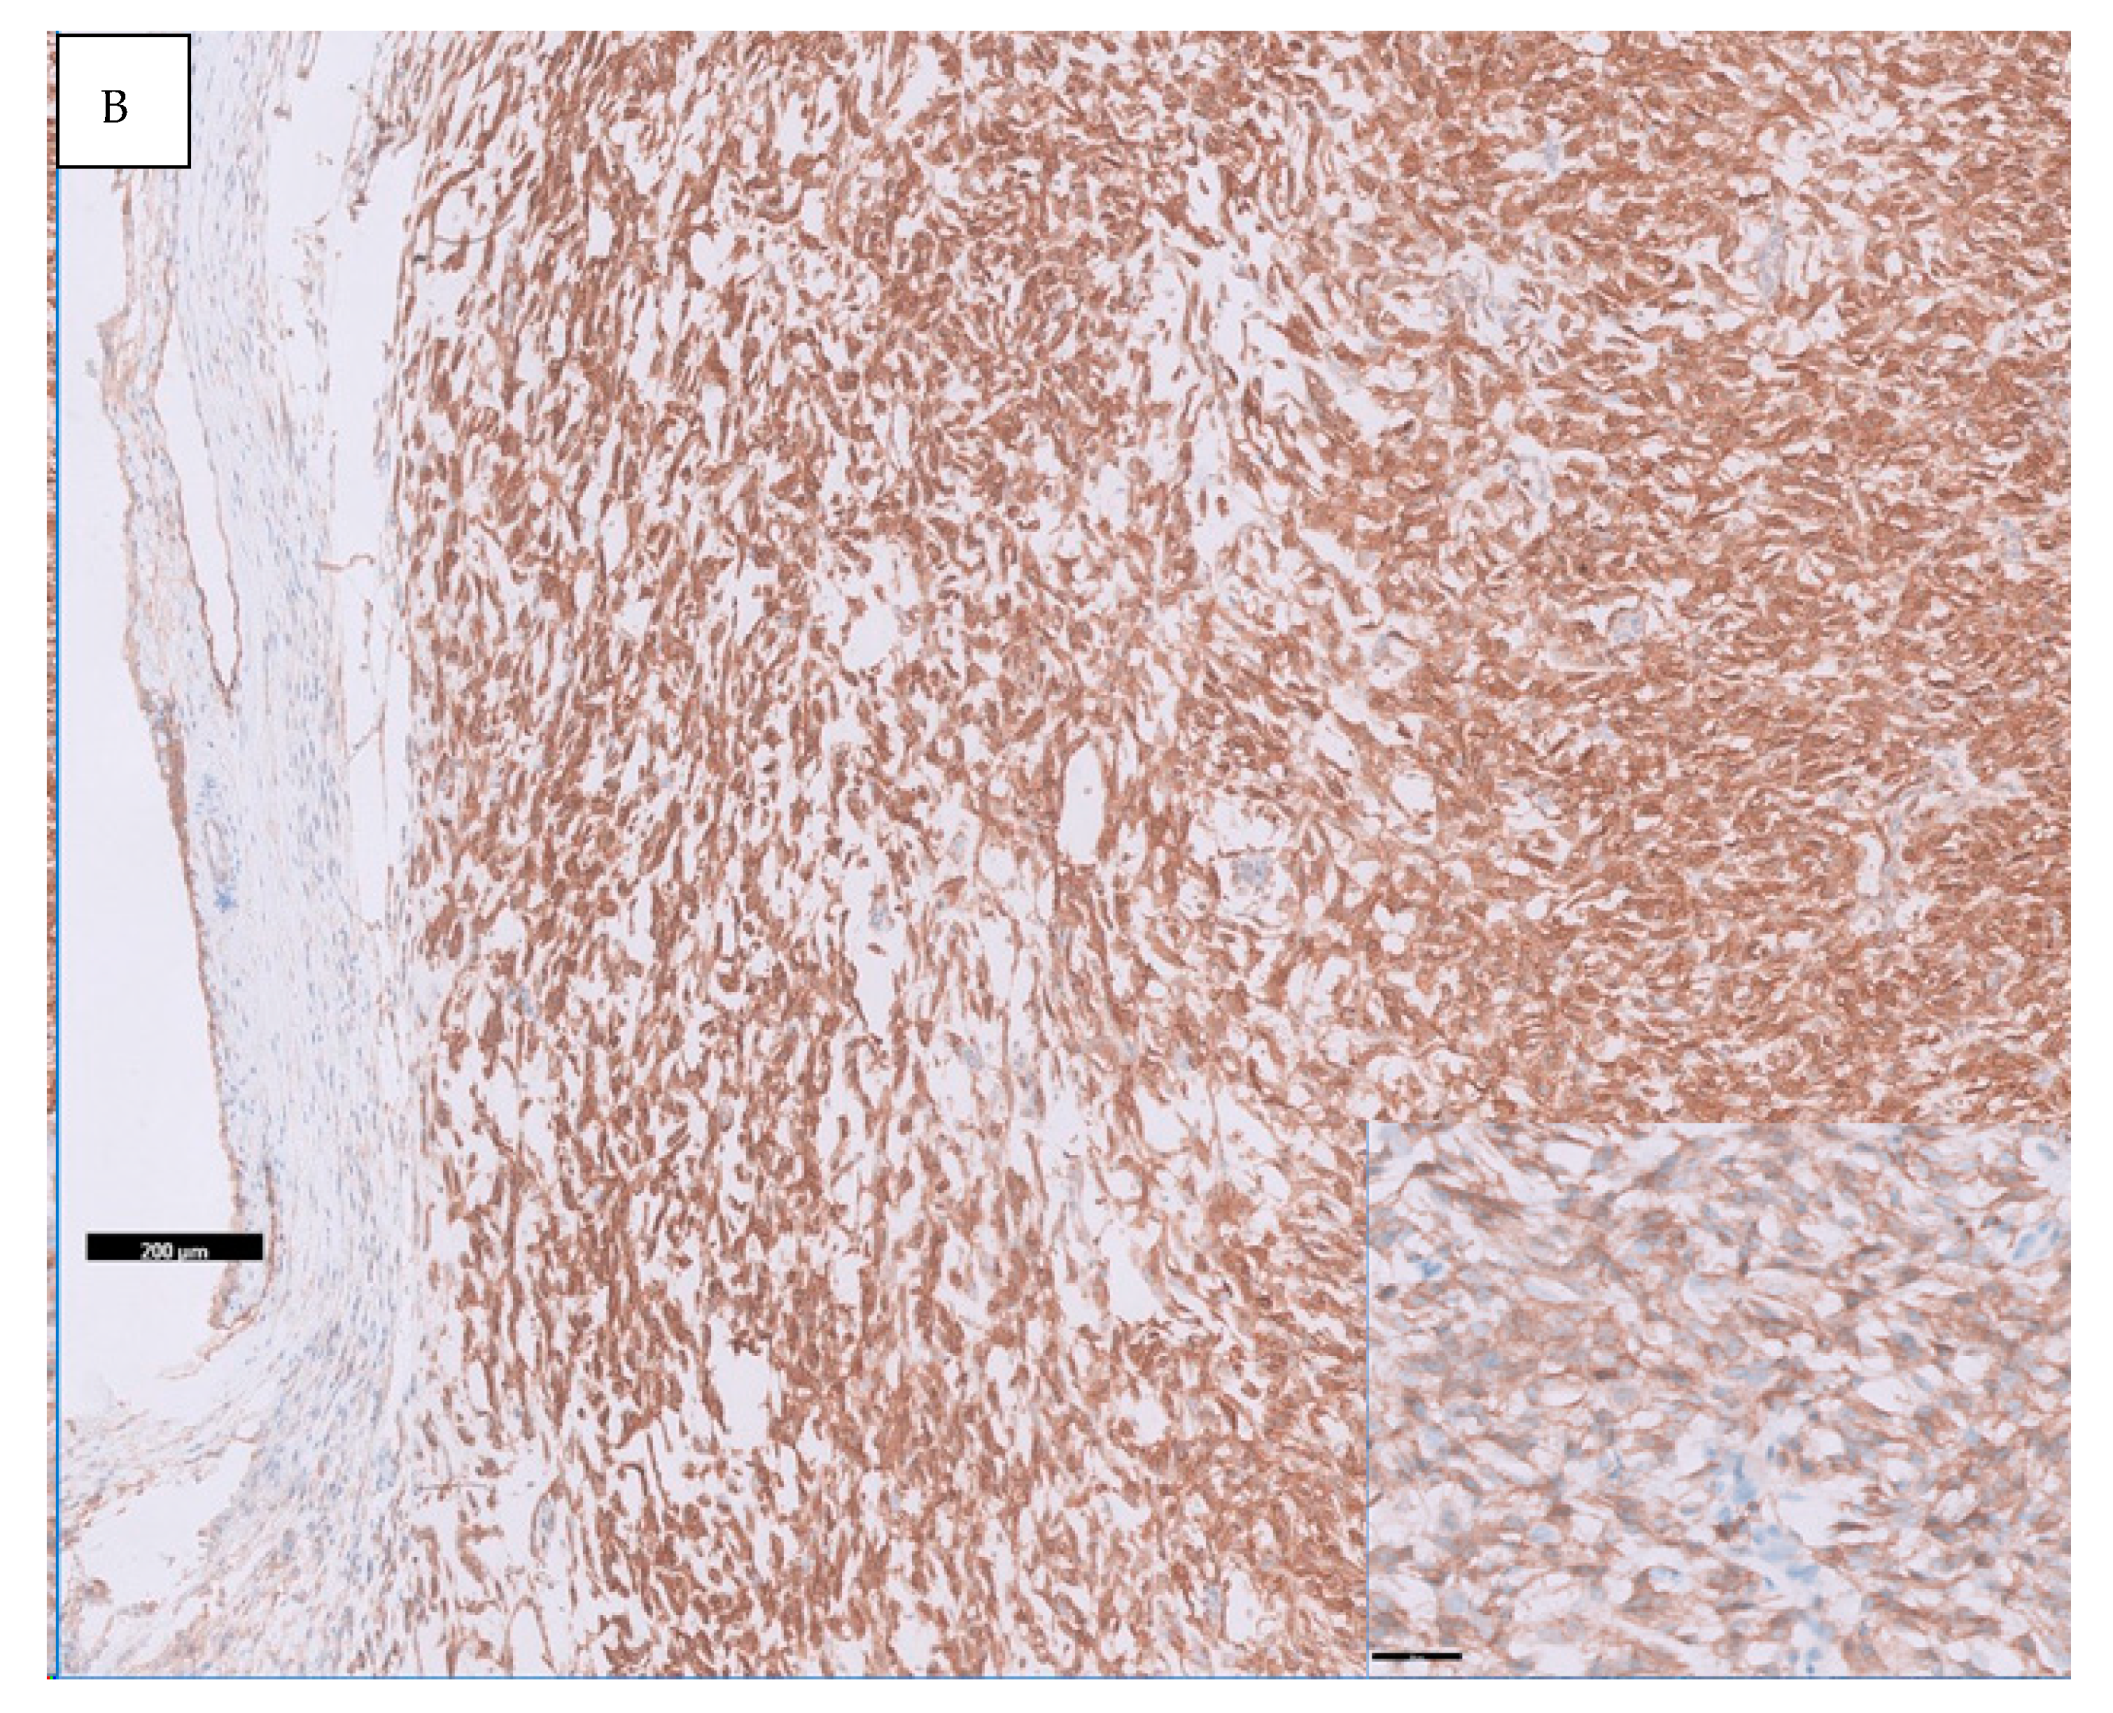

- Haller, F.; Knopf, J.; Ackermann, A.; Bieg, M.; Kleinheinz, K.; Schlesner, M.; Moskalev, E.A.; Will, R.; Satir, A.A.; Abdelmagid, I.E.; et al. Paediatric and adult soft tissue sarcomas with NTRK1 gene fusions: A subset of spindle cell sarcomas unified by a prominent myopericytic/haemangiopericytic pattern. J. Pathol. 2016, 238, 700–710. [Google Scholar] [CrossRef] [PubMed]

- Chiang, S.; Cotzia, P.; Hyman, D.M.; Drilon, A.; Tap, W.D.; Zhang, L.; Hechtman, J.F.; Frosina, D.; Jungbluth, A.A.; Murali, R.; et al. NTRK fusions define a novel uterine sarcoma subtype with features of fibrosarcoma. Am. J. Surg. Pathol. 2018, 42, 791–798. [Google Scholar] [CrossRef] [PubMed]